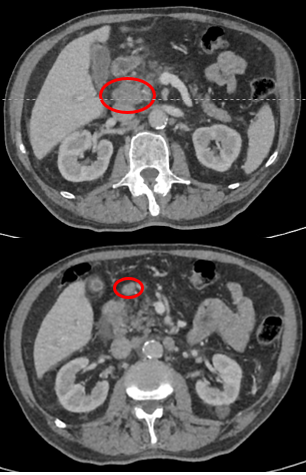

ПЭТ/КТ: апрель 2023